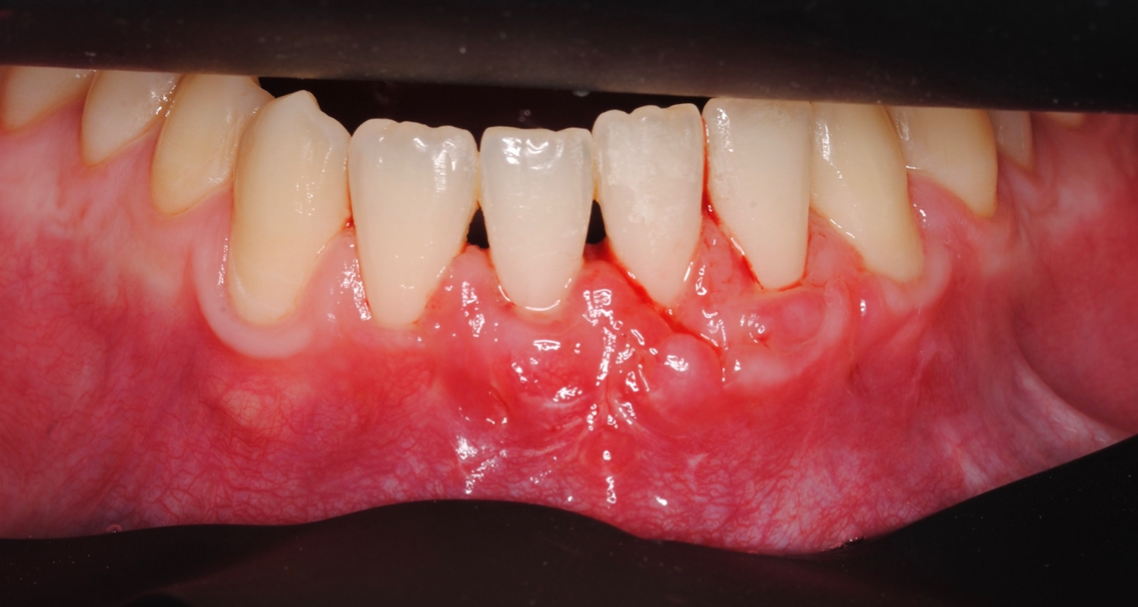

Os enseñamos este nuevo caso el Dr. Arturo Sánchez Colodro en nuestra clínica dental de Jaén, nos muestra un caso donde se puede apreciar con mucha claridad el antes y después de un caso de recesiones inferiores. Este caso ha sido tratado con la última y más avanzada tecnología en digitalización dental.

Objetivos periodontales:

- Cobertura radicular en recesión pieza 32.

- Mejora de la sensibilidad

- Estabilidad periodontal mejorando el biotipo gingival y aumento banda encía querantizada

ITC (Injerto tejido conectivo libre desepitelizado de paladar) + tunelización

Fotografías del proceso: